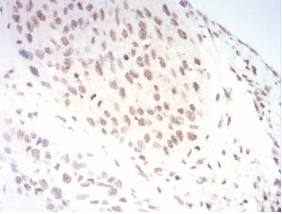

TERT Mouse Monoclonal antibody[3H2G9]

IHC    1/200 - 1/1000